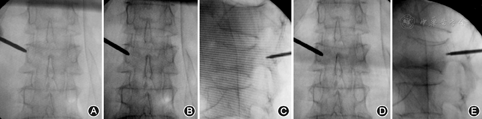

采用"一线影"基准定位法,在穿刺操作前调整X线球管的投照方向,使骨折椎体的终板呈"一线影",即骨折椎体的上/下终板在正侧位X线透视像上呈一直线,并且两侧的椎弓根影在正位透视像上以棘突为中心的对称分布,在侧位透视像上完全重叠(图1)。穿刺前对骨折椎体进行透视下定位,确定合适的穿刺点和穿刺路径,避免X线投照偏差造成穿刺失败。

以经双侧椎弓根穿刺途径为例。在正位X线透视下,首先将穿刺针针尖置于双侧椎弓根影的外上缘,左侧为10点钟、右侧为2点钟的位置,根据不同手术节段和骨折类型,选择恰当的穿刺点和穿刺方向,缓慢地锤击穿刺针。当正位透视穿刺针针尖位于椎弓根影的中线时,侧位透视穿刺针针尖应该抵达椎弓根影前后径的1/2。继续锤击进针,当正位透视穿刺针针尖接近椎弓根影的内侧缘时,侧位透视针尖应抵达椎体后壁,然后继续进针2~3 mm,完成穿刺(图2)。